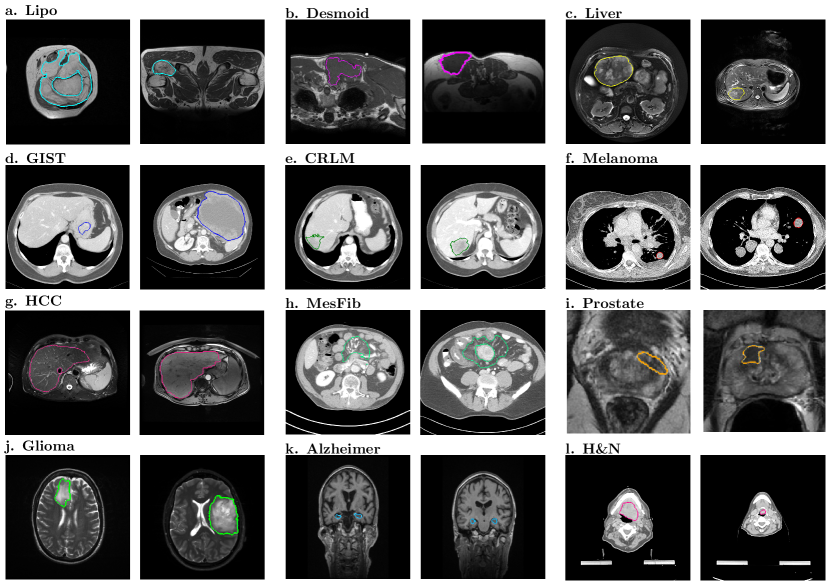

In order to evaluate our WORC framework, experiments were performed on twelve different clinical applications: see Table 2 for an overview of the twelve datasets, and Figure 2 for example images from each dataset. We focused on oncology applications as these are most common in radiomics, but also included a widely known non-oncology application (Alzheimer) to demonstrate the application of our framework. For the oncology applications, we used routinely collected, clinically representative, multi-center datasets to train and evaluate our biomarkers. This facilitates generalization of the resulting biomarkers across image acquisition protocols and thus across clinical centres, increasing the feasibility of applying such a biomarker in routine clinical practice.

For each experiment, per patient, one or more scan(s) and segmentation(s), and a ground truth label are provided. All scans were made at “baseline”, i.e., before any form of treatment or surgery. One dataset (the Glioma dataset) consists of a fixed, independent training and test set and is thus evaluated using 1000x bootstrap resampling. In the other eleven datasets, the performance is evaluated using the random-split cross-validation.

Error plots of the AUC from the application of our WORC framework with the same default configuration on the twelve different datasets are shown in Figure 3; detailed performances, including other metrics, are shown in Table 3; the ROC curves are shown in Figure A.2. In eleven of the twelve datasets, we successfully found a prediction model, with mean AUCs of 0.83 (Lipo), 0.82 (Desmoid), 0.80 (Liver), 0.77 (GIST), 0.61 (CRLM), 0.75 (HCC), 0.80 (MesFib), 0.72 (Prostate), 0.71 (Glioma), 0.87 (Alzheimer), and 0.84 (H&N). In the Melanoma dataset, the mean AUC (0.45) was similar to that of guessing (0.50).